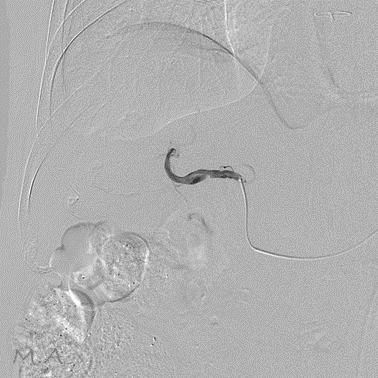

血管撮影装置

当院は令和6年3月の新病院発足に伴い、より高精度で安全な検査・血管内治療(IVR:Interventional Radiology)を提供するため最新の島津製作所製バイプレーンシステムTrinias B12s(Opera smart)を導入しました。

平面型X線検出器(FPD:Flat Panel Detector)を搭載し、カテーテルを用いた高度な血管内治療においてより少ないX線で高い解像度の画像を描出可能となりました。

バイプレーンシステムを採用したことにより、一回の造影剤注入で2方向撮影が可能となり、従来のシングルプレーンと比較して造影剤使用量を半分程度に抑えることができ、被ばくを低減すると共に検査時間の短縮にも繋がり、より患者さまの負担を軽減することが可能となりました。

冠動脈造影検査(CAG:Coronary Angiography)をはじめ、経皮的冠動脈インターベンション(PCI:Percutaneous Coronary Intervention)、下肢動脈のインターベンション(EVT:Endovascular Treatment)、肝動脈化学塞栓術(TACE:Transcatheter Arterial Chemo-Embolization)等、心血管領域、腹部血管領域における高度なカテーテル治療においてその性能を発揮しております。